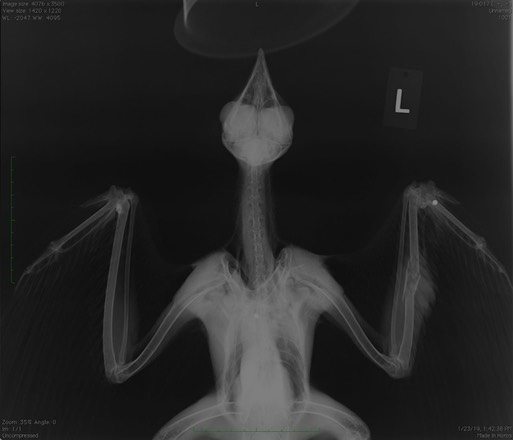

Red-tailed Hawk 19-017

Witnesses saw this young hawk being shot near Halfway, OR. They reported the incident to authorities and then were directed to Blue Mountain Wildlife. An exam and radiographs revealed three pellets in the hawk, a fracture of the left ulna (the pellet passed through the wing) and an injured eye. It appears that a pellet entered the hawk’s right eye and exited through the eyebrow. There is also damage in the hawk’s left wrist. It is too soon to know if he will be releasable. Hopefully there will be consequences for those who shot the hawk.